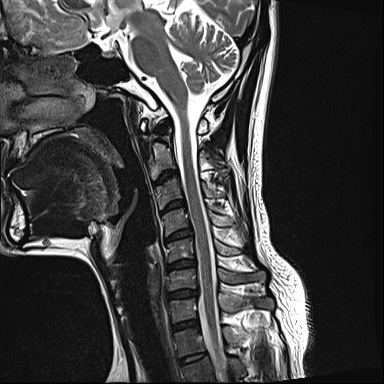

Ű 177 64 40 ()ijħ ڸǥغ ǥغ ϱ ȣϴ 1C.ٸǷ 6C.ڸ 6C.ھ Ḳ 6C.ڻ ()ũ( ߰Ż) ڸ(߹) ĿCڸ(ĸ) Ը ũ(߰Ż)ġ, , Ḳ ġ Ǵ ġ ()ijħ ڸǥغ ǥغ ϰ ߴ ġ 2008~2011 ð ɾƼ ǻ ۾ Ҷ, Ʈ , ȸ ϰ, . 2011 4 : 6,7 ߰Ż , ڸ ó ļ ַ ġ . ü, ߳, ѹ, ũ, ֻġ ġ غ ȿ ġ ġᰡ Ұ Ǵϰ ֿ 3ȸ ƮĪ ణ ȣ. 2014 5 20 濡 ħ ڱ ϰ · ư. (ֱ ϰ, Ʈ ϰ ) а ũ ִ ֺ, Ʒ κп δֻ 1ȸ ̰, ణ . ûϸ鼭 ȸԲ ϴ ûϰ ߽ϴ. Ϻϰ ȸ ּ. mriԴϴ. |